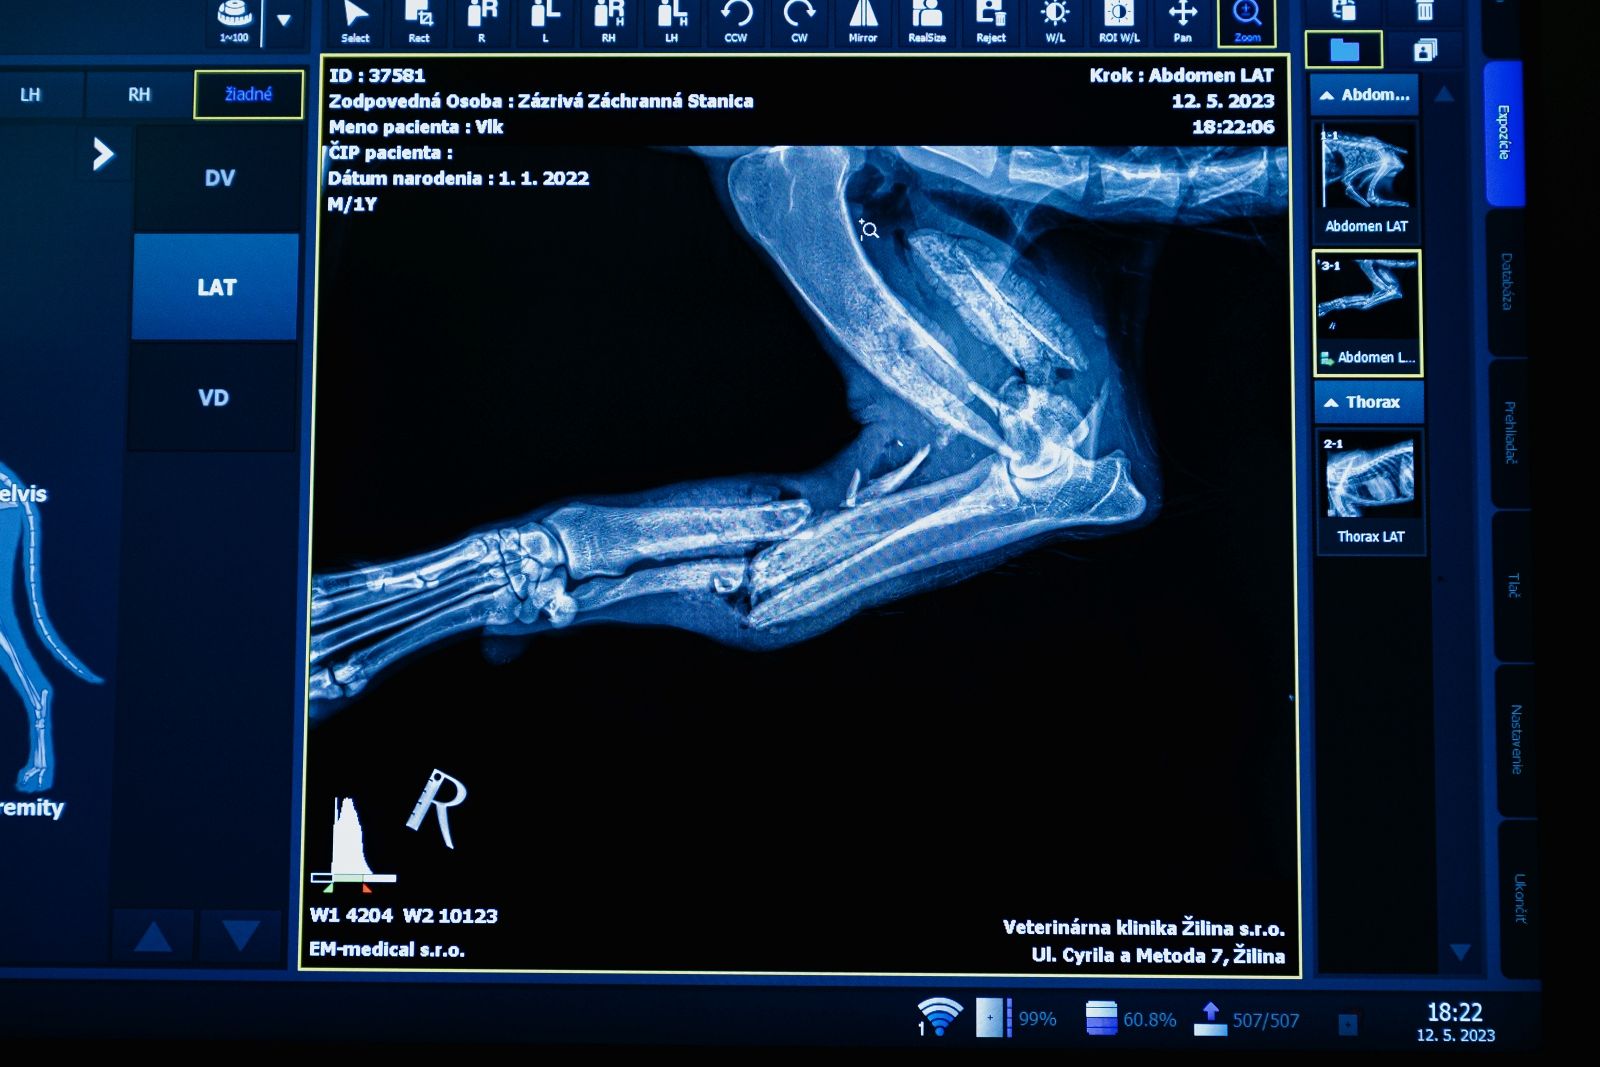

„Včera sme na klinike vyšetrili odchyteného vlka s traumou hrudnej končatiny. Žiaľ povaha zranenia, celkový výživový stav vlka z Nízkych Tatier a sekundárna infekcia boli natoľko zlé, že sme museli pristúpiť k eutanázii,“ potvrdili slová záchranárov žilinskí veterinári.

Vĺčka vyšetrovali na Veterinárnej klinike v Žilina. Snažili sa mu pomôcť. Žiaľ, nešlo to.